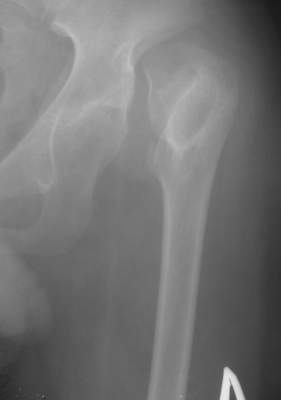

"Поздний" (14 лет) врожденный вывих (подвздошный) бедра |

Dear collegues,Мальчик, 14 лет. Из Узбекистана...Никакой документации на данный момент нет, но со слов выяснилась приблизительно следующая картина... Патологию диагностировали в 2 года...якобы она была двусторонней (скорее всего дисплазия справа и вывих слева),лечили то ли функционально то ли закрытым вправлением под наркозом...как бы то ни было около года гипсовался в различных позах по-Лоренцу...Потом вроде бы повязка сломалсь (слева) и родителям сообщили о рецидиве вывиха...С тех пор (с 3 лет) никак не лечился...С возрастом стало возникать укорочение левой н. конечности, что особенно то и не беспокоило как выяснилось...2 года назад (12 лет) появились боли в левом тазобедренном суставе (на стороневыцвиха)...Вот это то (боли) и являются главной причиной обращения в данное время (14 лет).Укорочение левой н. конечности на 5 см не воспринимается как главная проблема...Снимки в приложении.Что делать?